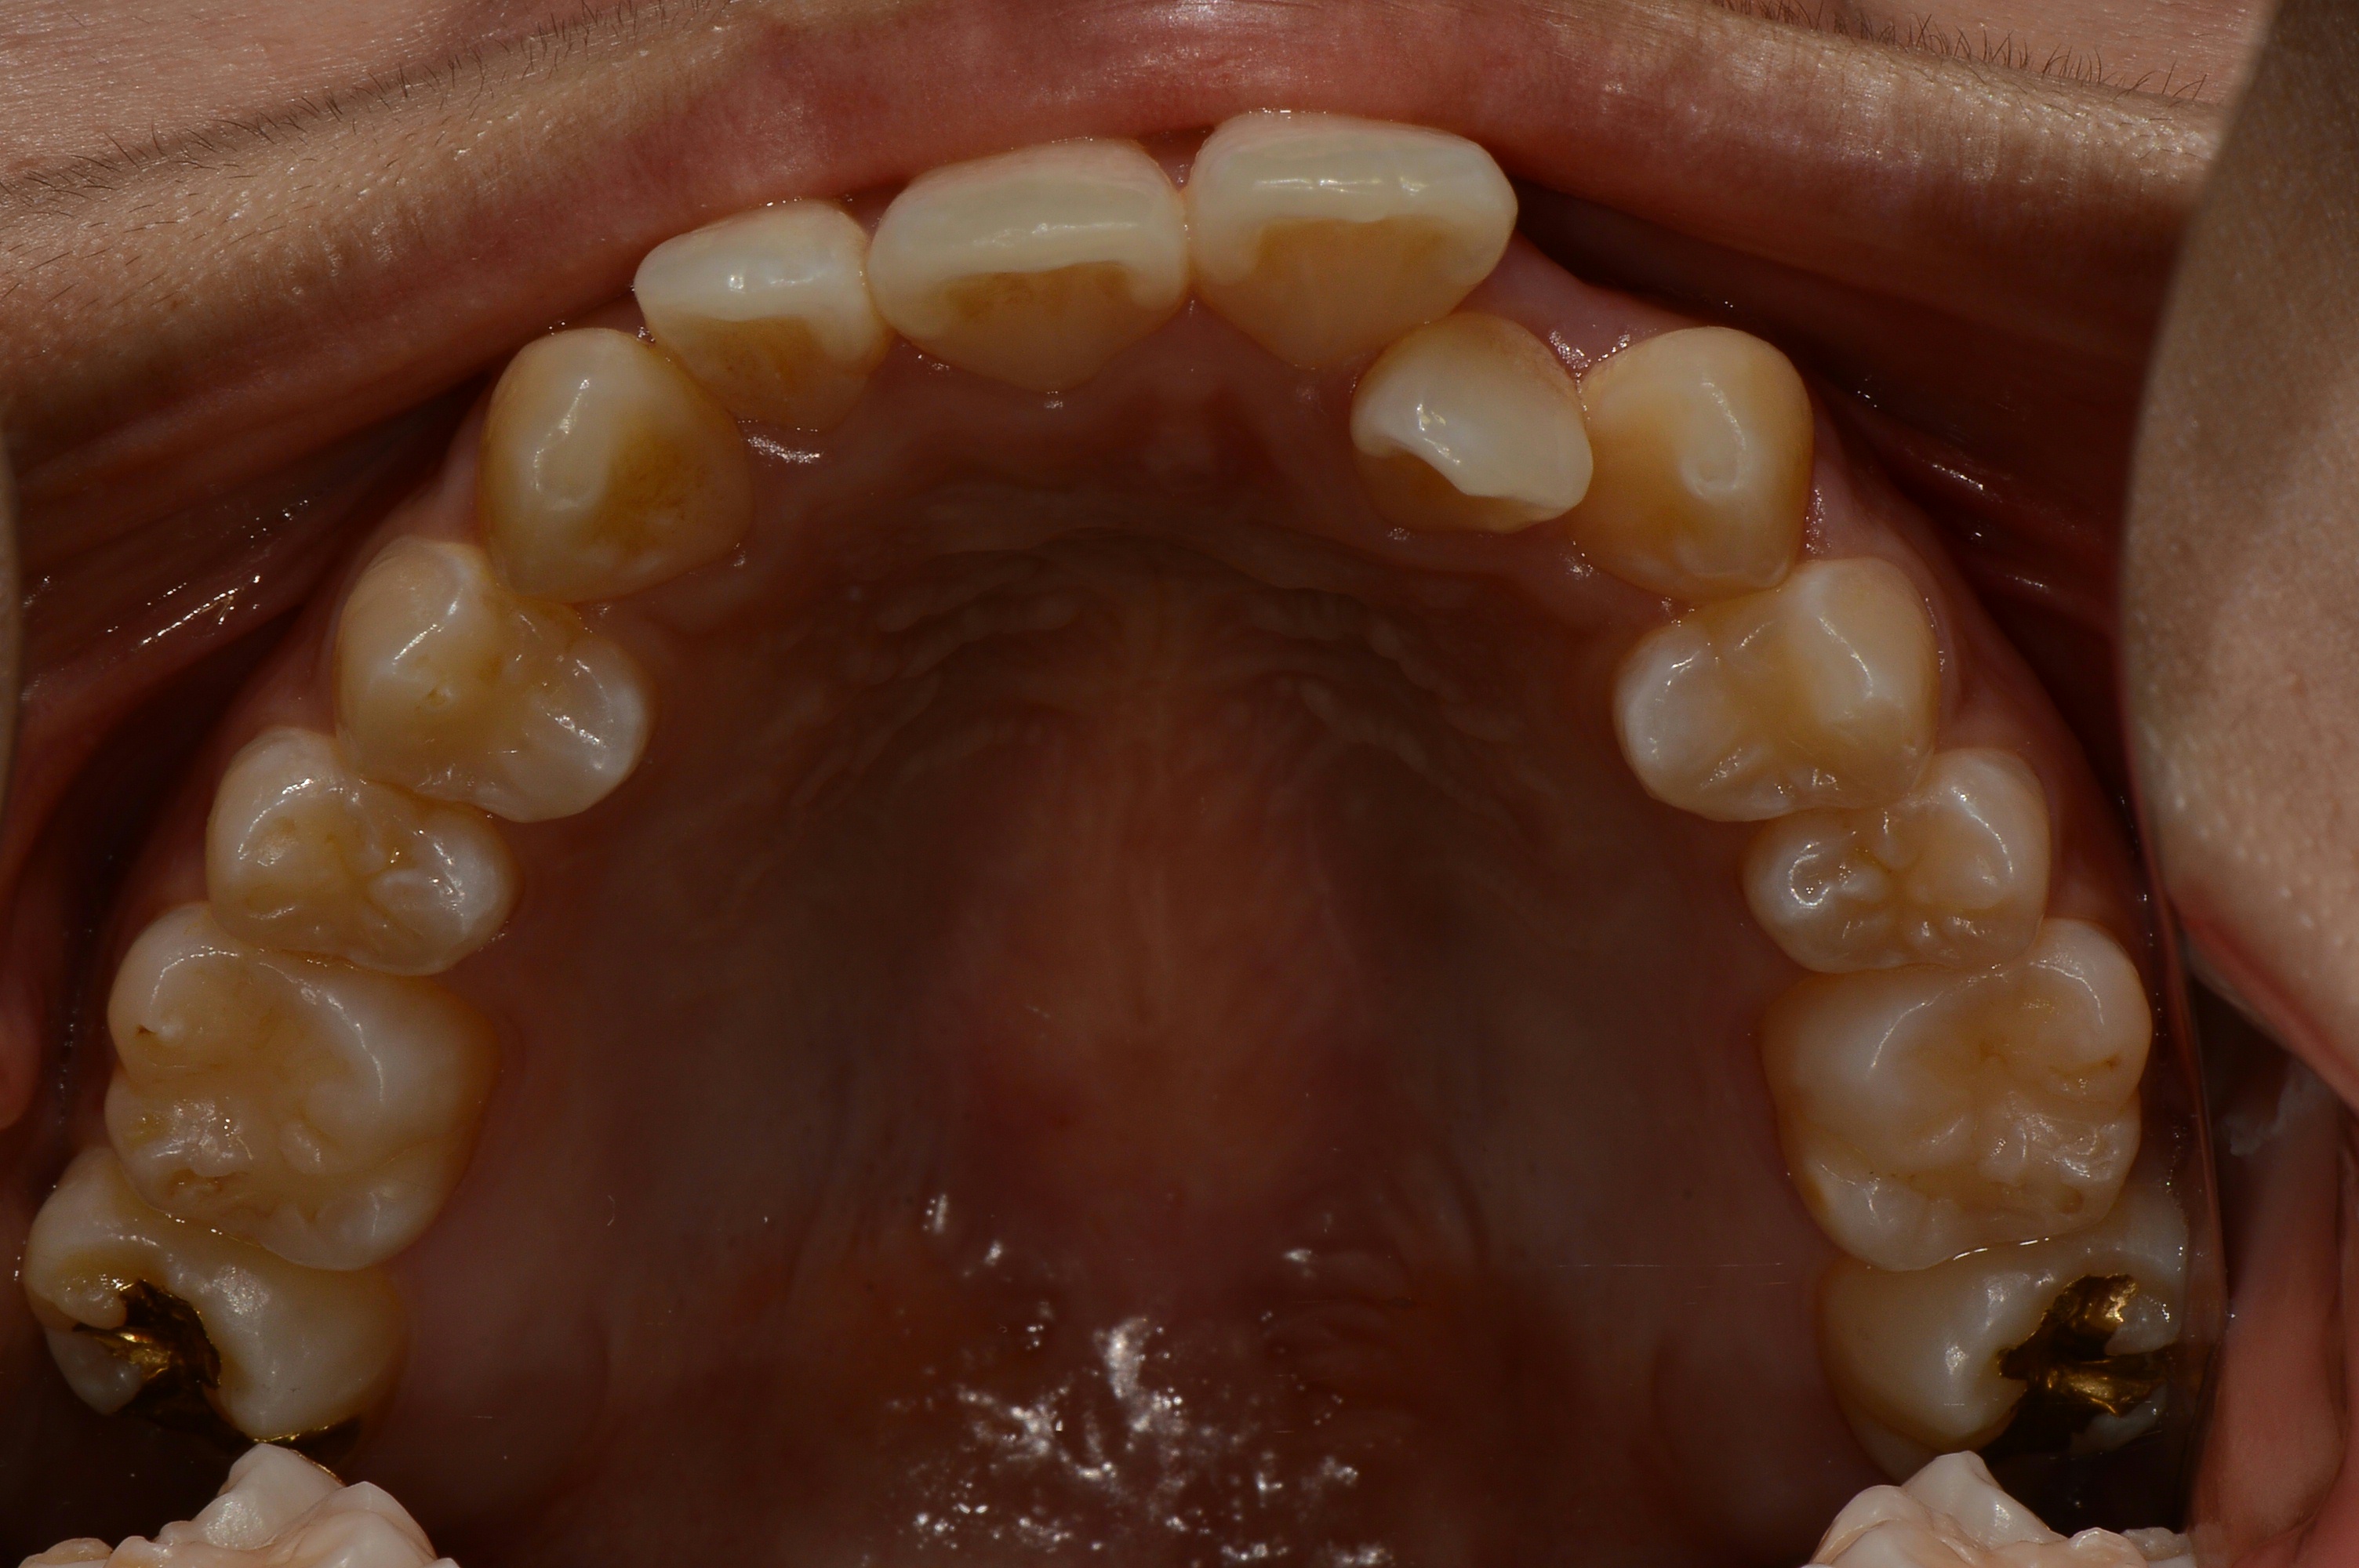

치료 전 사진입니다.